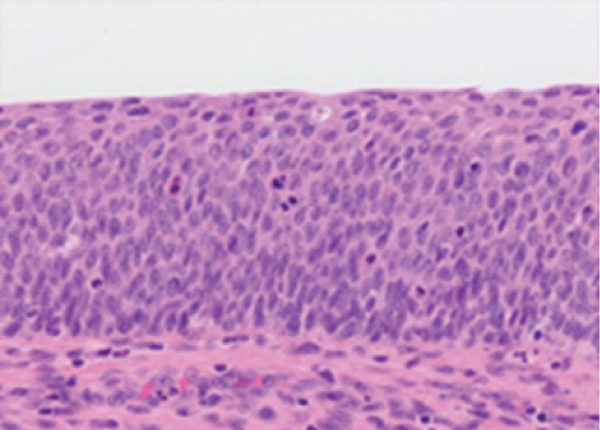

Figure 2: Carcinoma cervix (HSIL) delineating nuclear hyperplasia, hyperchromatic nuclei and full thickness atypia with few mitotic figures [6].

6. Image 2 Courtesy: Pathology outlines.